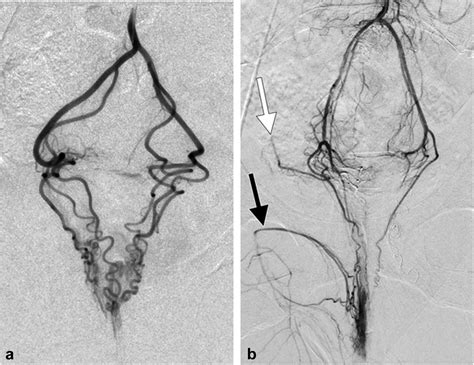

Hemorrhoid Artery Embolization is a cutting-edge, image-guided procedure performed by interventional radiologists. Unlike traditional surgery, which physically removes the hemorrhoidal tissue, HAE works by targeting the blood supply that feeds the hemorrhoids. By reducing the arterial blood flow to the hemorrhoidal plexus, the procedure causes the hemorrhoids to shrink over time, effectively alleviating symptoms like bleeding, pain, and protrusion.

Because it is a minimally invasive technique, it does not require general anesthesia or incisions in the sensitive anal region. Instead, a tiny catheter is guided through a blood vessel in the wrist or groin to the specific arteries supplying the hemorrhoids. Small particles are then injected to block these vessels, successfully reducing the pressure and engorgement of the hemorrhoidal tissues.

2. Guidance: Using real-time X-ray imaging (fluoroscopy), the radiologist navigates a microcatheter through the vascular system.

3. Embolization: Once the specific hemorrhoidal arteries are identified, specialized embolic agents are injected to reduce the blood supply.